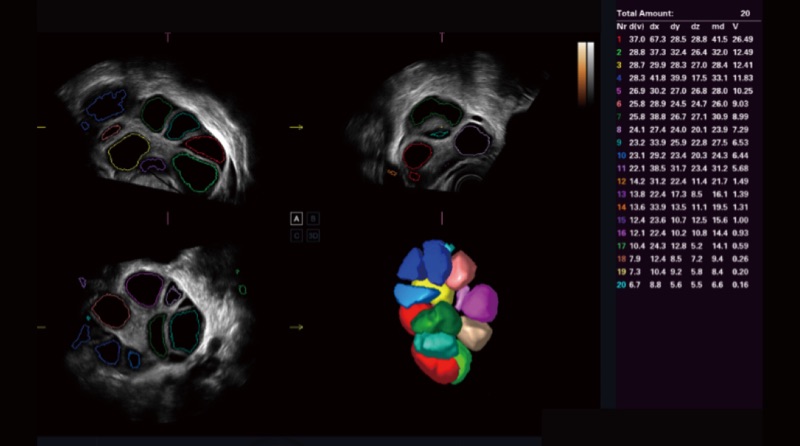

AVC Follicle ermöglicht eine hohe Effizienz bei der Follikelanalyse. Es handelt sich um eine volumenbasierte automatische Berechnung der Anzahl und des Volumens der Follikel. Die Follikel werden in den Ergebnissen nach Größe sortiert und in verschiedenen Farben dargestellt, um die Visualisierung zu verbessern.